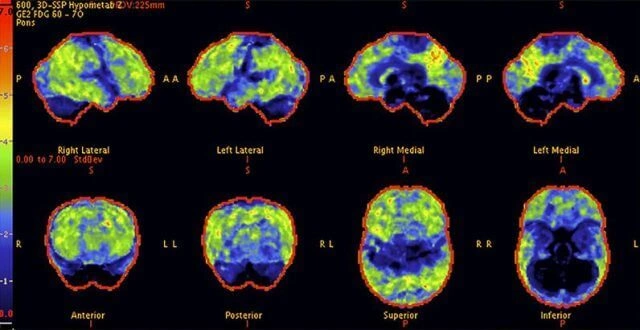

Above: A

68-year-old woman with a 10-year history of cognitive issues. Previous PET scans

showed significant metabolic decline, indicating Alzheimer's.

Above: The patient's PET scan after CureFight treatment shows improvement, with cognitive abilities greatly enhanced as the scan approaches that of a normal brain.